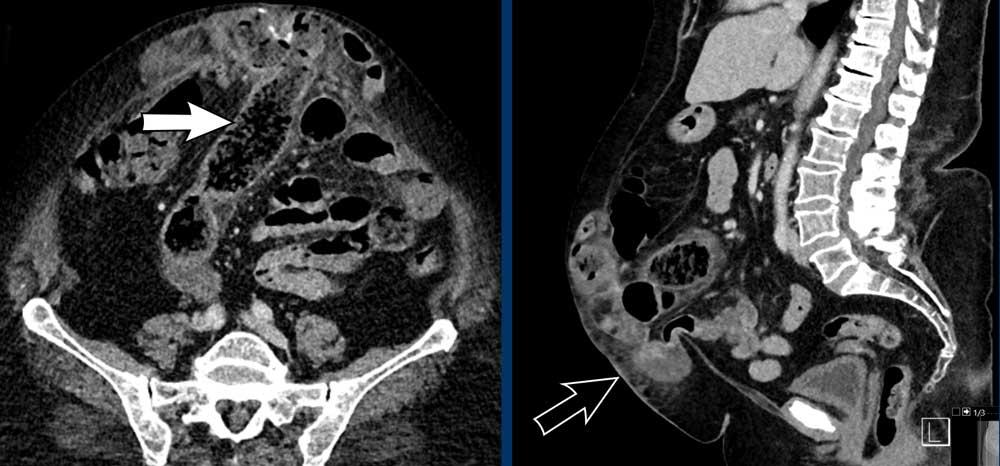

Bệnh nhân này có khối thoát vị chứa ruột non.

Lỗ thoát vị khá nhỏ và có hẹp tại điểm ruột đi vào túi thoát vị (mũi tên vàng) và tại điểm ruột thoát ra khỏi túi thoát vị (mũi tên trắng).

Hai vị trí hẹp này là bằng chứng của tắc ruột quai kín.

Có giãn ruột và thâm nhiễm mỡ do thiếu máu cục bộ gây ra bởi tắc nghẽn tĩnh mạch.

Đây là một ví dụ khác về tắc ruột quai kín trong túi thoát vị.

Mũi tên trắng chỉ vị trí tắc nghẽn đầu tiên, nơi ruột đi vào quai kín.

Mũi tên vàng chỉ vị trí thoát ra.

Trong trường hợp này, quai kín được tạo ra bởi các dải dính trong túi thoát vị.

Lưu ý tình trạng thâm nhiễm mỡ và các quai ruột giãn với thành ruột tăng tỷ trọng nhẹ.

Đây đều là các dấu hiệu của thiếu máu cục bộ ruột.

Phẫu thuật mở bụng cấp cứu đã được thực hiện ngay lập tức.

Đoạn ruột trong túi thoát vị bị thiếu máu cục bộ và có màu tím, nhưng sau khi gỡ bỏ các dải dính, màu sắc của ruột đã trở lại bình thường.